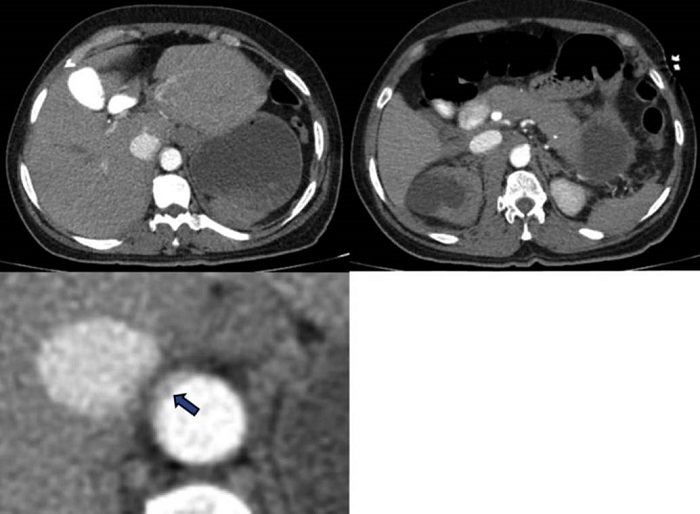

Caso clínico

Paciente de 59 años de edad con cuadro clínico de 4 días de evolución consistente en dolor lumbar irradiado a abdomen. Es remitida para valoración, sin antecedentes personales o familiares de importancia. En el examen físico, el paciente está en condiciones generales regulares, taquicárdica, con masa palpable y pulsátil a la exploración abdominal. Se procedió a la realización de angioTC de abdomen. En la fase arterial se observó dilatación aneurismática de la aorta abdominal infrarrenal con un alcance de diámetro de hasta 94 mm con comunicación de la luz entre la aorta abdominal y la vena cava inferior sugestivo de fístula aortocava (Figura 1).

Fue posible identificar la extensión del aneurisma abdominal hasta la bifurcación de las arteria ilíacas adyacente a la VCI en todo su recorrido abdominal (Figura 2). Adicionalmente se observó ausencia de realce del parénquima renal derecho por hipoperfusión y cambios inflamatorios periaórticos con hematoma retroperitoneal asociado (Figuras 3 y 4).

Opacificación temprana de la VCI en la fase arterial 8.

Pérdida de los planos grasos entre la aorta y la VCI 8.

Aumento del diámetro de la VCI 8.

Visualizar la comunicación anormal entre la aorta y la vena cava 6.

Signos adicionales que soportan FAC son la hipoperfusión renal y la ruptura del aneurisma 5. El trabajo de Navdeep Singh y colaboradores concluyó que la presencia simultánea de contraste en la aorta y la VCI durante la fase arterial es el signo diagnóstico más importante; sin embargo, muy a menudo el aneurisma comprime la VCI, lo que dificulta la evaluación de este signo 5.